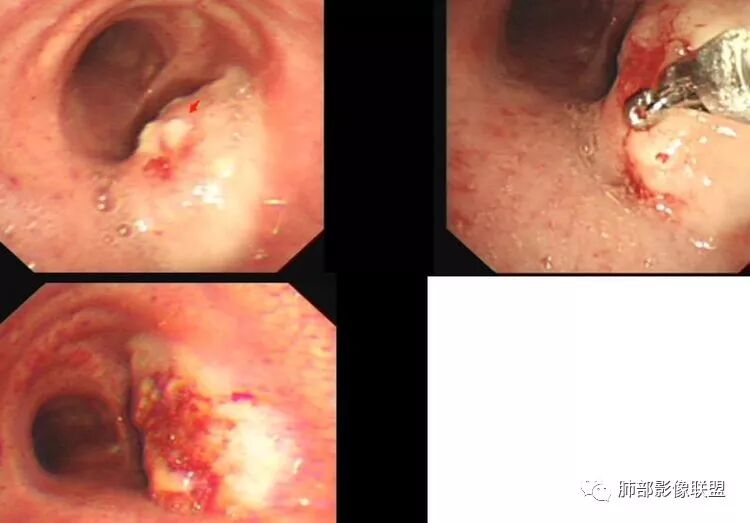

THINKER:隆突上气管右侧壁肿物,镜下表面不光滑,有苔,C下似有冰山征,考虑类癌

穿越气海的风:气管内肿物,气管镜见肿物表面凹凸不平,考虑气管鳞癌

张帅:中年男性,体检发现,病变位于气管下1/3,以管腔内生长为主,向管壁、管腔外浸润。气管镜:气管下1/3可见新生物,表面呈结节状,可见少量白色坏死物。粘膜充血水肿不明显。病理怀疑病灶内有纤维组织,细胞成梭形(具体不会)。此区域以鳞癌及腺样囊性癌多见,结合病理基本可排除此诊断

雪狐7305:中年男性,体检发现,气管下段肿瘤,向腔内生长,向管壁、管腔外浸润。气管镜见气管下段新生物,表面少量坏死物。常规会考虑鳞癌,病理未见典型神经内分泌性肿瘤细胞和腺癌细胞,病理不熟悉啊,怀疑病灶内有纤维组织,似乎有鳞状上皮细胞,不典型增生?鳞癌?

病例小结      气管神经鞘瘤属于罕见的气管良性肿瘤,一般气管良性肿瘤或腔内或腔外生长的结节样改变,恶性肿瘤呈腔内外生长,但本例肿块向腔外生长,呈“冰山样改变”,即肿瘤的腔内部分较小而腔外部分较大,无周围组织侵犯。因此肿瘤腔内外生成不能作为鉴别气管良恶性肿块的绝对依据。        因此冠(矢)状位多平面观察、软骨是否破坏、气管壁有无增厚等细节观察,对于鉴别气管肿块良恶性有重要的参考性。

1.气管隆凸上右前壁不规则结节影,部分突入腔内,南边老师观察有推挤软骨环“破土而出”的形态特征。注意没有沿气管粘膜表面生长蔓延的生物学行为。

3.男性气管内肿瘤以发生于粘膜上皮的鳞癌最为常见,本例没有软骨破坏,病灶没有沿气管粘膜表面生长蔓延不支持。